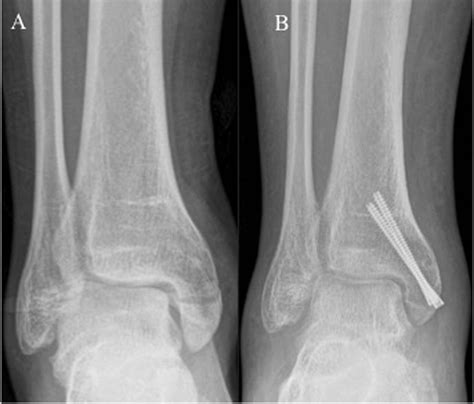

• X-rays: Standard X-rays can reveal the presence and extent of the fracture. Multiple views may be taken to get a comprehensive picture.

For more severe fractures, especially those involving displacement or multiple fragments, surgery may be necessary. Surgical options include:

• Open Reduction and Internal Fixation (ORIF): This procedure involves realigning the bone fragments and securing them with plates, screws, or rods.